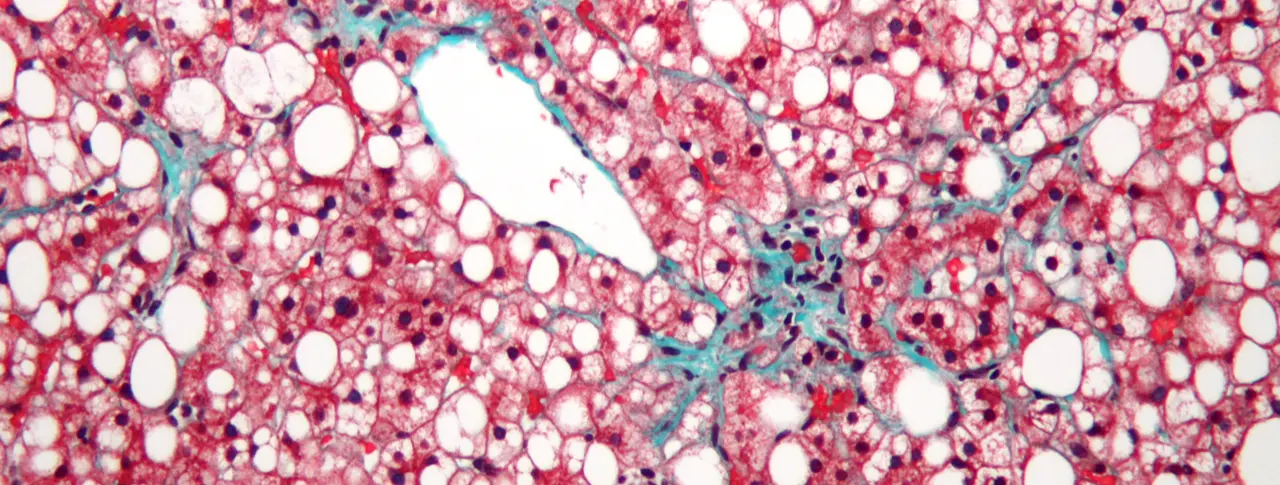

Main image: This liver tissue from a patient with non-alcoholic fatty liver disease (NASH) shows mild fibrosis (green), which can lead to advanced liver scarring called cirrhosis. Image: Nephron/Wikimedia